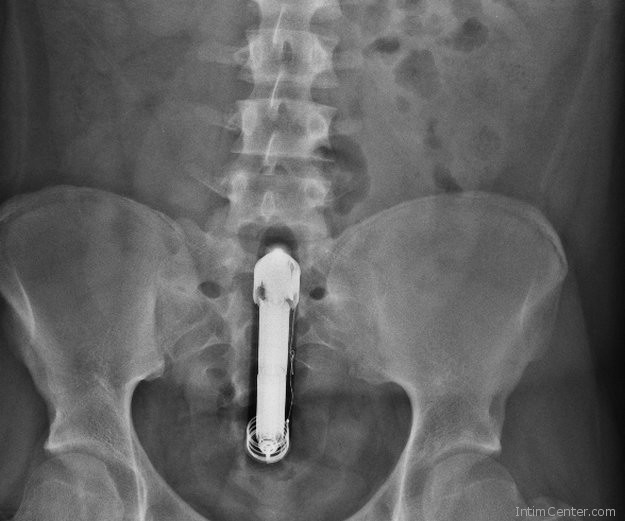

– Belenéztem a sürgősségis ápolónő szemébe, és így szóltam, nem cifrázom, egy vibrátor van a fenekemben – jelentkezett be a kórházból, később hozzátéve, hogy a nővérke a legkedvesebb emberi lény, akivel valaha találkozott, és megtudta tőle, hogy más is várakozik ott dildóval a végbelében. Meg is röntgenezték, várakozás közben pedig 2600 követője egyik-másikával poénkodott.

A röntgen után még mindig nem szedték ki a vibrátort, viszont Grawlyt bent tartották éjszakára. Másnap délelőtt megvolt a beavatkozás. Hét órán át működött az elem. Hősünket amúgy pelenkásan bent tartották megfigyelésre, de már hazaengedték, jól van. A tanulság, hogy vigyázzunk a végbélnyílás izgatásával, vannak olyan eszközök, amelyeken egy perem talalható, ami megakadályotta a becsúszást.